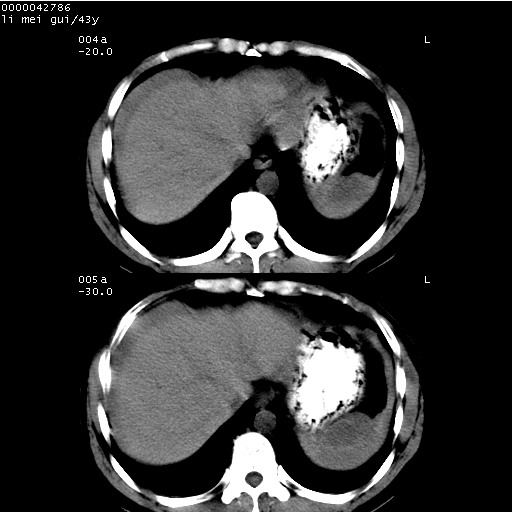

| 患者,男,43岁。突发腹痛2小时,面色苍白,难以平卧。自述近期无明确外伤史,为摩托车驾驶员。 腹部b超检查:脾脏中上极回声异常,肿瘤待排。 临床诊断:腹痛原因待查。 上中腹部ct轴位平扫+增强扫描(层厚10mm,螺距1.0,重建间隔10mm),图像如下: ![]() ![]() ![]() ![]() ![]() ![]() ![]() ![]() ![]() ![]() ![]() ![]() ![]() ![]() ![]() ![]() ![]() ![]() ![]() ![]() ![]() ![]() ![]() ![]() ![]() ![]() ![]() ![]() ![]() ![]() ![]() ![]() ![]() ![]() ![]() zrs发言:支持脾破裂 wwp发言:支持脾破裂并腹水。 xulianj发言:脾脏肿瘤破裂可能性大 zsl6918发言:不像肿瘤出血,考虑还是与外伤后引起的慢性出血有关 zzyy发言:平扫见肝周及脾周积液,脾内密度不均。脾内肿瘤较少见。还是外伤性脾破裂。 沈丘东方医院发言:脾门区一个不均匀强化病灶与其周液体相连多考虑脾占位破裂出血 yixianman001011发言:脾破裂并腹水是可以肯定的,具体原因多以肿瘤性破裂出血,脾脏淋巴瘤可能性大. 结果: 术后,经详细询问患者,其仔细回忆:一月前骑摩托时左侧腰部与别人有“轻微”触碰,因责任在自已,当时又无明显不适,未引起注意。 临床术后诊断:脾破裂并失血性休克(1.外伤性迟发性脾破裂。2.脾脏肿瘤破裂?) 术后标本病检:脾破裂并出血,未见明显肿瘤成份。 原贴地址:http://www.radinet.com.cn/forum_view.asp?forum_id=4&view_id=34070 |